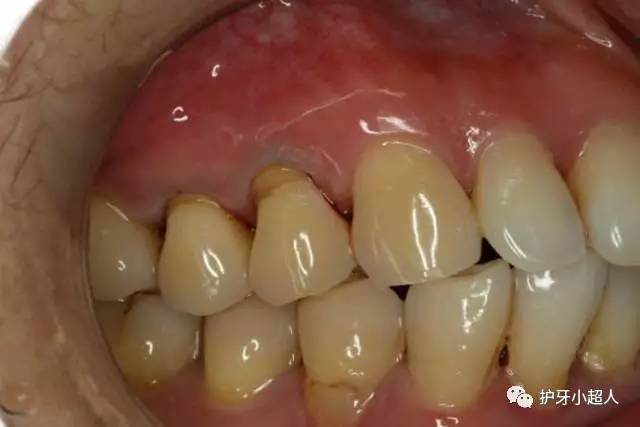

不过除了龋齿会造成牙洞,牙齿根部的楔形缺损也会导致牙洞发生。牙齿楔形受损,就是在牙齿颈部、根部位置产生缺损,形成楔子形状的缺口,以其形状而称之为牙齿楔形缺损。

造成牙齿根部楔形受损的原因主要有以下两个方面的原因:一是牙刷刷毛过硬,对牙齿的损害力强,日积月累,就会出现牙齿楔形受损;第二则是因为刷牙的方式,大部分人刷牙的方式都是横向的,而且刷牙的力度特别大,在用一部位向同一个方向持续作用力,造成牙齿楔形受损。一般来说,牙齿楔形受损是在牙齿的颈部和根部,因为这两个部位的牙釉质相对稀薄,更易受到损害。

一旦形成牙齿楔形受损,脆弱的牙根暴露,极易成为牙菌斑欺负的对象。长此以往,食物残渣在此堵塞,类似于蛀牙牙洞,刷牙很难去除,进而变质变酸,腐蚀牙齿;腐蚀从牙齿颈部开始,在此将牙齿腐蚀断裂,缺损变为整个牙冠,形成牙洞。